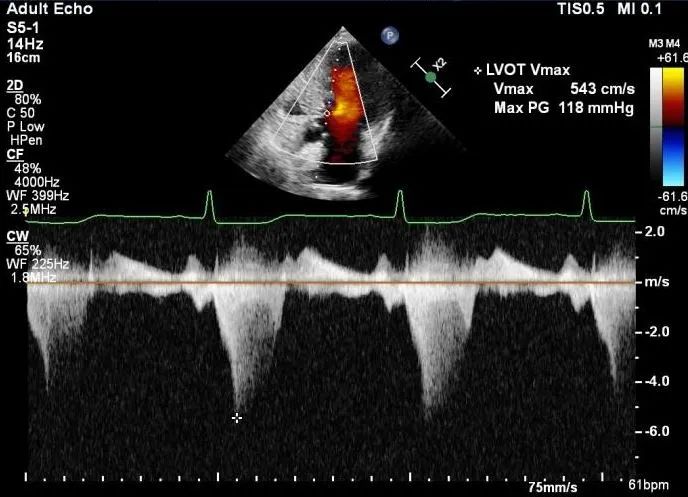

患者是一位70岁的女性, 超声提示,患者室间隔最大厚度为20.8mm,静息状态下左室流出道重度梗阻,压差为118mmHg。负荷状态下122mmHg。

术后左室流出道压差